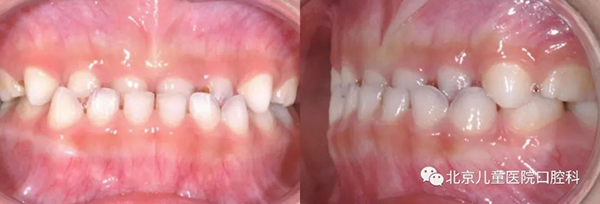

三、恒牙期(12岁以上)

大部分常见的错颌畸形在这个阶段都可以进行矫正,但对于骨骼畸形的矫形治疗相对有限,所以建议孩子第一次到口腔正畸科就诊检查的时间还是要提前哦!早发现,早干预,让孩子拥有一口整齐的牙齿和更漂亮的面容吧!